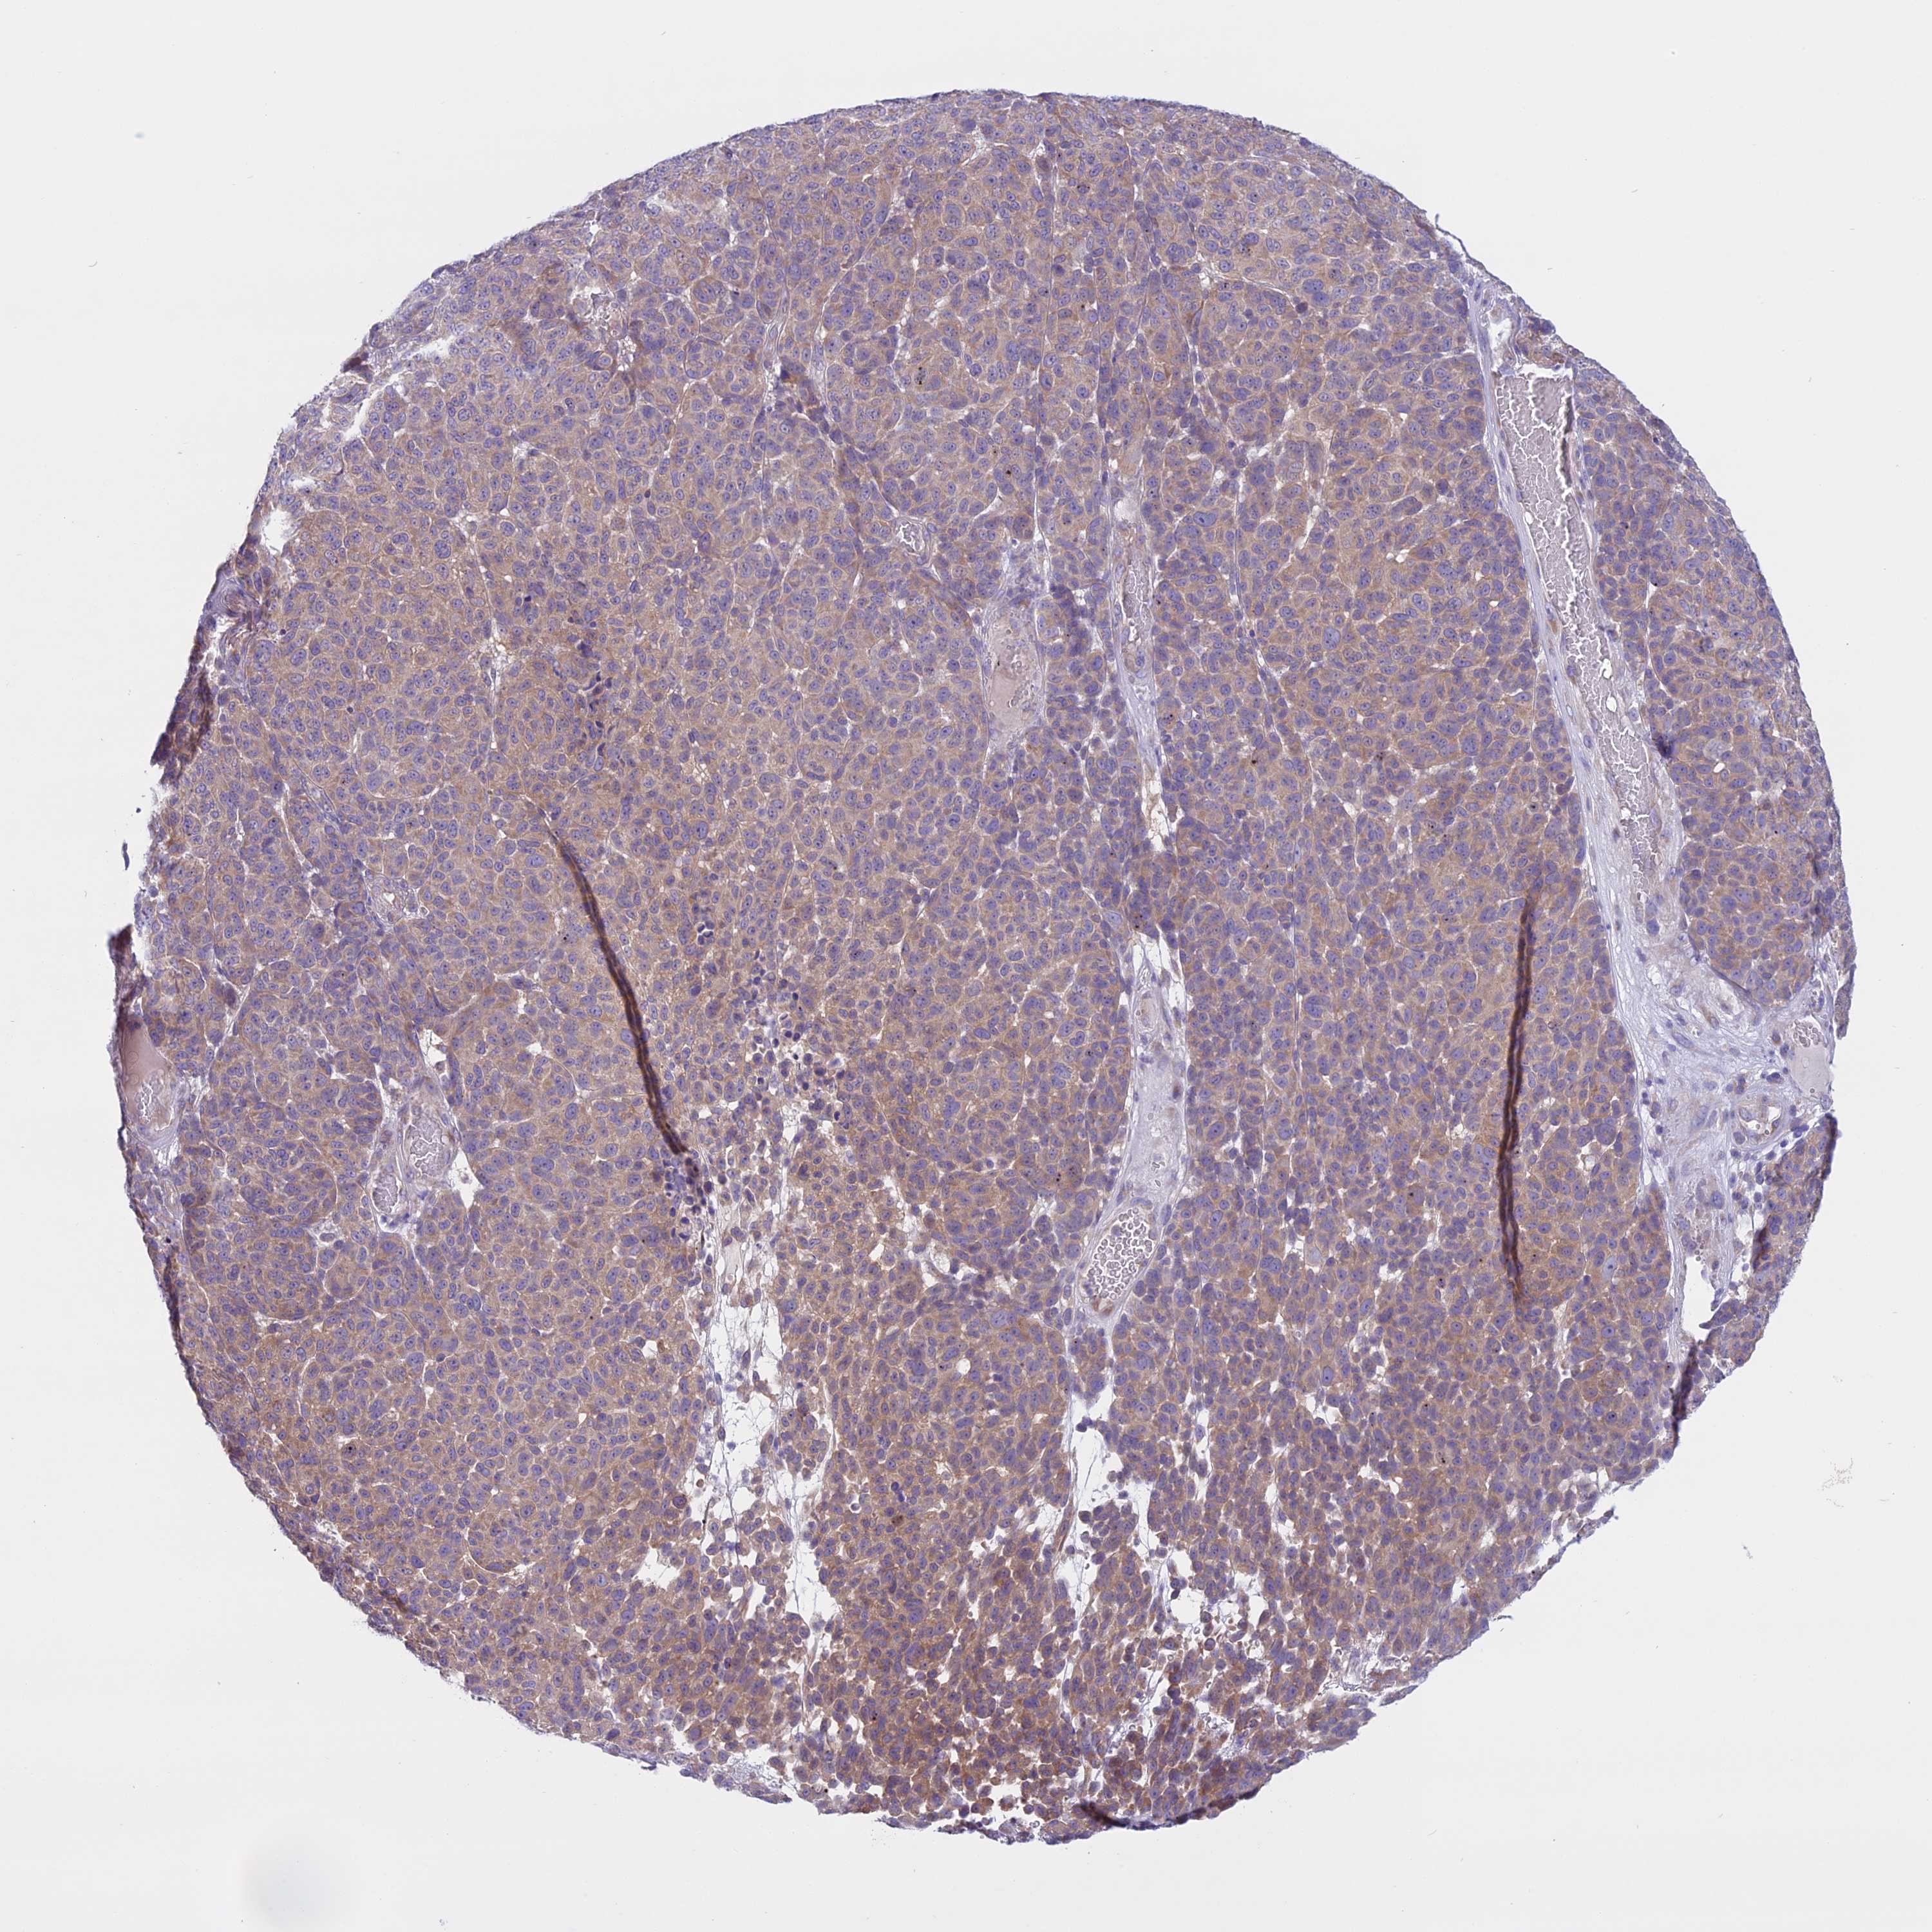

MELANOMA - Protein expressioni

A mouse-over function shows sample information and annotation data. Click on an image to view it in a full screen mode. Samples can be filtered based on level of antibody staining by selecting one or several of the following categories: high, medium, low and not detected. The assay and annotation is described here.

Note that samples used for immunohistochemistry by the Human Protein Atlas do not correspond to samples in the TCGA dataset.

Antibody stainingi

Antibody staining in the annotated cell types in the current human tissue is reported as not detected, low, medium, or high, based on conventional immunohistochemistry profiling in selected tissues. This score is based on the combination of the staining intensity and fraction of stained cells.

Each image is clickable and will lead to virtual microscopy that enables deeper exploration of all samples and also displays staining intensity scores, fraction scores and subcellular localization as well as patient and tissue information for each sample.

Antibody HPA042003

Staining

High

Medium

Low

Not detected

Intensity

Strong

Moderate

Weak

Negative

Quantity

>75%

75%-25%

<25%

None

Location

Nuclear

Cytoplasmic/membranous

Cytoplasmic/membranous,nuclear

Malignant melanoma, NOS

Malignant melanoma, Metastatic site